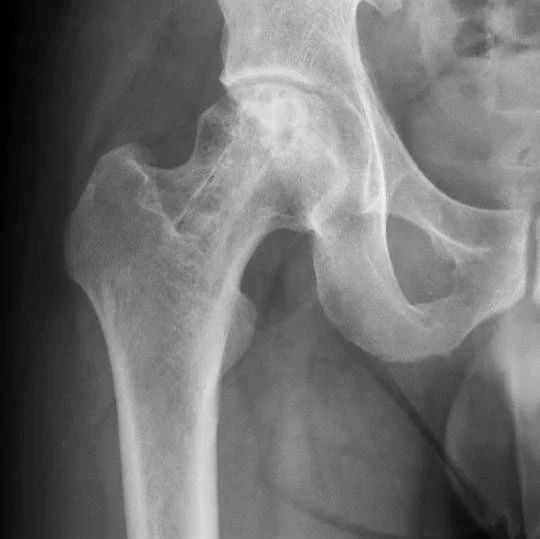

【为家学医课堂】股骨头缺血性坏死的手术疗法(三)

股骨头缺血性坏死争取早发现早治疗,根据股骨头坏死程度分期,1期的话避免负重,配合中药、理疗可以获得不错的效果。2、3期需要根据具体情况来进行相应的手术治疗。